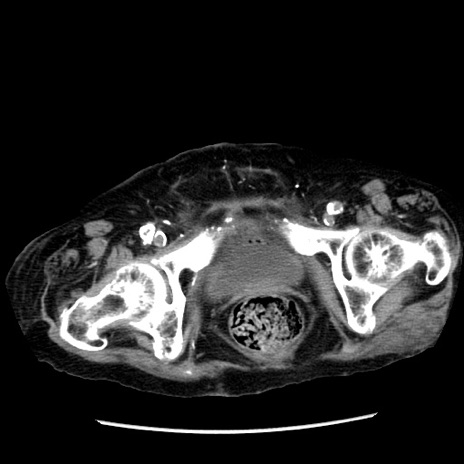

冠状断像

【症例】 90歳代女性

【主訴】 腹痛・嘔吐

【現病歴】今朝から左側腹部痛を認めた。 経過観察していたが、嘔吐を認めたため来院。

【既往歴】 子宮癌術後

【身体所見】 意識清明、BP 127/54mmHg、P 98bpm Sp02 95%(RA)、BT 35.8°C、腹部平坦・軟腸ぜん動音聴取良好、右下腹部圧痛(+) 反跳痛なし

【データ】WBC 9800、CRP 0.46